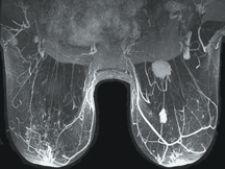

“Over the last year, we have seen more than an 80 percent growth rate in the number of MR procedures for breasts,” noted Lindsey Carver, GE marketing manager for MR. “It is very actively increasing for two reasons. One is because there have been a lot of reviewed articles published about breast imaging and physicians are feeling more confident about prescribing that procedure. Secondly, because the technology has made tremendous improvements in the last few years.”

GE’s MR solution, Vibrant, performs a bilateral breast exam in both the sagittal and axial planes with the same resolution and scan time as a single-breast MR study. “If you do detect cancer in a patient, then you want to know whether that cancer is localized, a single lesion or if there are many lesions,” Carver pointed out. “You need to study both breasts because in about five percent of patients they will have lesions in both breasts.”